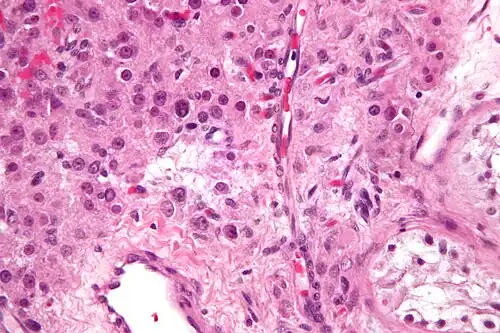

Micrograph of a Leydig cell tumour

Micrograph of a Leydig cell tumour